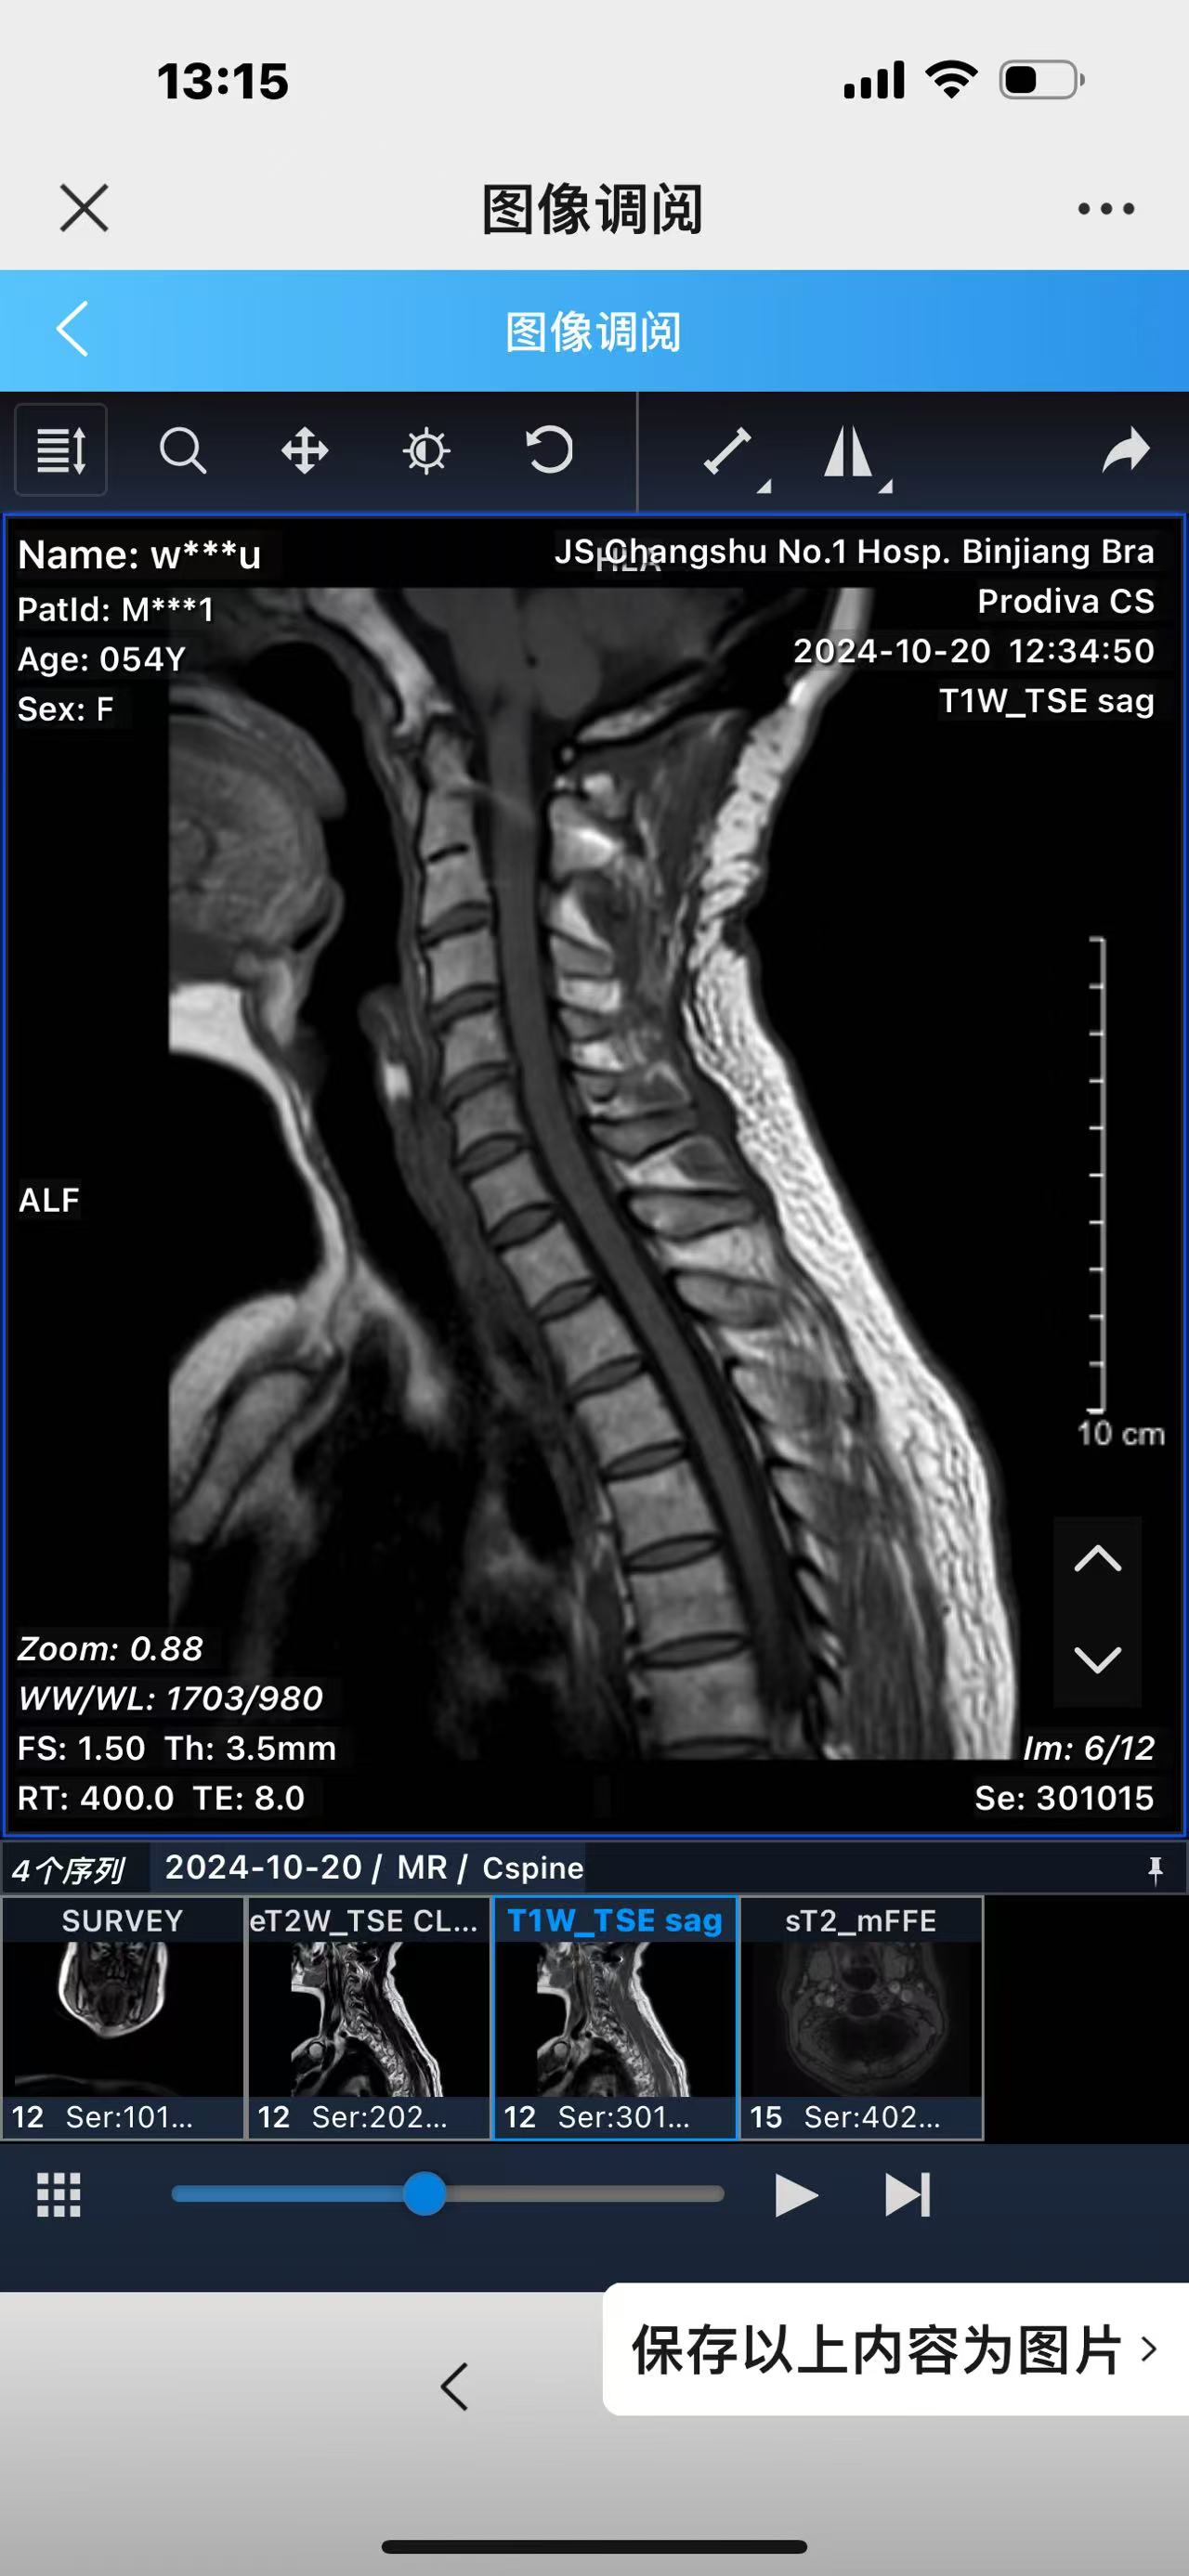

• 诊断:寰枢椎脱位,颅底凹陷

• 影像:

• 2024.10.20,复查,对位良好,偶尔会肩甲骨酸,坐下就不酸。